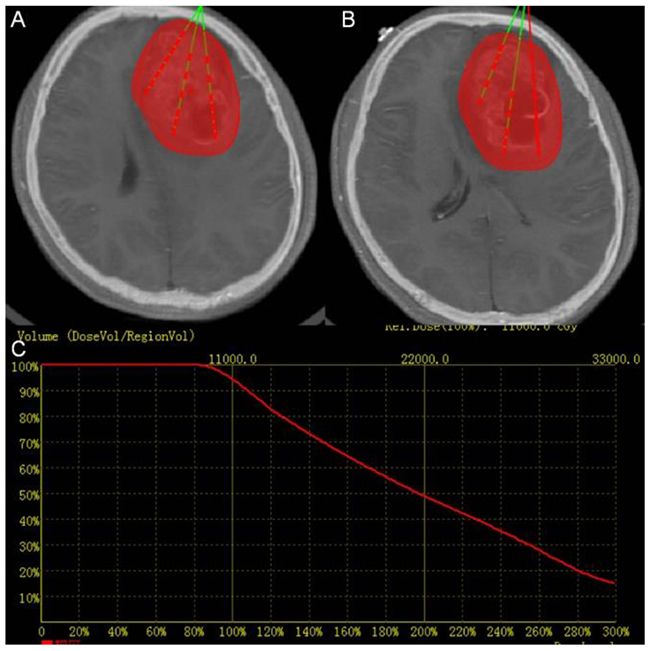

The example of a 24 years old female patient with HGG in the cerebral frontal lobe is used to illustrate the process. Visible margins of the tumor are outlined manually, and inverse treatment planning [39] is used (Figure 2).

Figure 2: Treatment planning. (A) and (B) Two slices of CT-MRI fused images showing the PTV in red and planned catheter and seed placement in green (C) Dose volume histogram of PTV of pre-operation treatment planning. The red curve shows the dose volume histogram of the target.